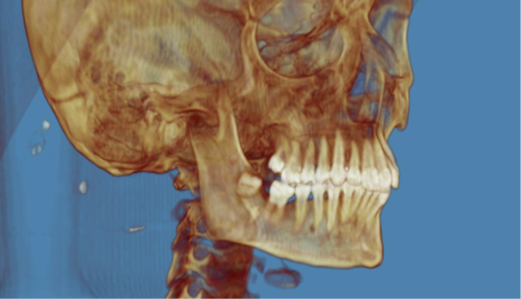

Bilateral Comminuted Mandibular Fracture Caused by Gunshot Wound: Case Report Using Prototyping to Assist Surgical Planning

Julia Tavares Palmeira, Diego Learth Lima, Ricardo Franklin Gondim, José Maria Sampaio Menezes Junior, Clarice Maia Soares de Alcântara Pinto

bjcr30